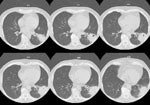

A CT scan of the chest demonstrated a large, cavitary infiltrate extending to the pleural surface within the left lower lobe. Sputum cultures and bronchoalveolar lavage yielded no organisms. Norcardia was cultured from a percutaneous specimen.